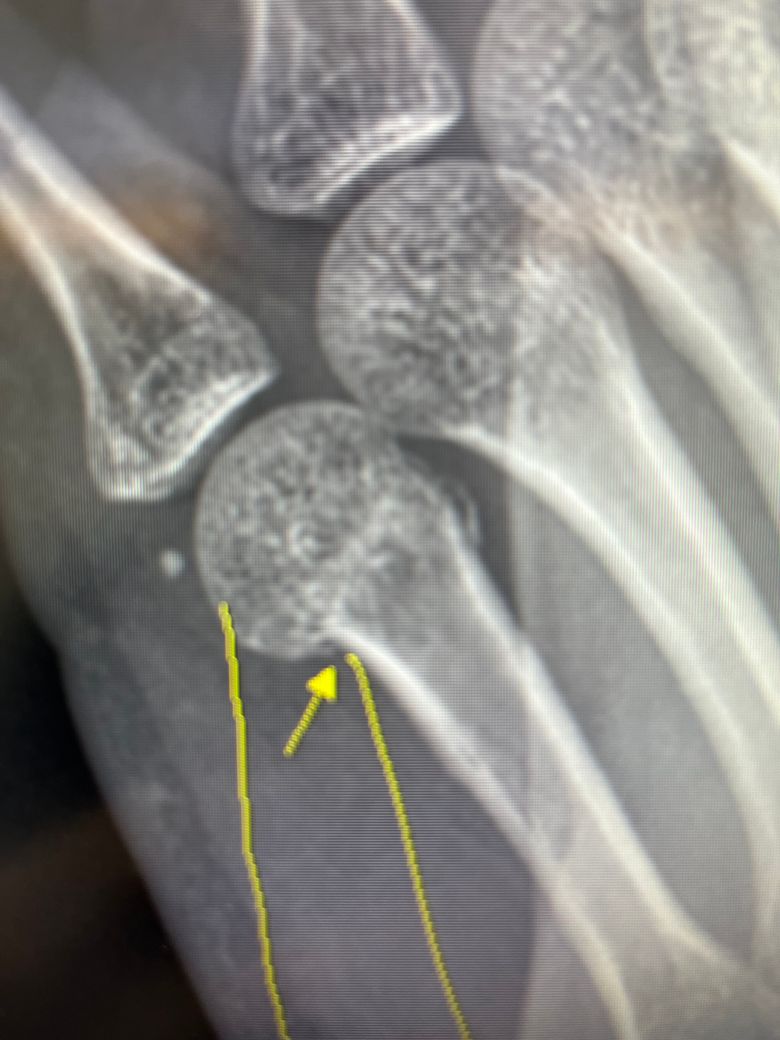

지난주 목요일 친구와 장난을 치다가 철문을 오른손 주먹으로 가격한 이후 부어올라 동네 병원을 방문했더니 복서골절이라는 진단을 받았습니다

교정치료를 진행하고 교정이 잘 되지않아 수술을 하여야 할 것 같다며 큰병원으로 가라고 이야기해주셨는데요 해당 골절의 경우 수술이 꼭 필요할까요? 통증도 별로 없고 많이 붓지도 않아 저는 최대한 깁스만으로 회복하고 싶습니다.

• 2번 째 사진

복서골절은 골절 각도, 뼈의 어긋남, 손가락 기능 제한 여부에 따라 수술 여부가 결정됩니다. 통증이 적어도 골절이 심하게 휘었거나 관절 정렬이 틀어지면 수술이 필요할 수 있습니다.

굴곡 각도가 30~40도 이상인 경우나 혹은 손의 회전 변형이 발생하거나 복합골절 또는 골편 간 간격이 크거나 비수술적인 치료를 하였지만 효과가 없거나 하면 수술적인 치료를 고려해볼 수 있습니다.

통증이 적다고 해서 괜찮은 것은 아니며 손의 작은 뼈는 신경이 덜 자극되는 위치라서 심한 골절이어도 통증이 약할 수 있으며 나중에 기능장애가 생기면 되돌리기 어려워 초기에 잘 맞춰 놓는 것이 매우 중요합니다.